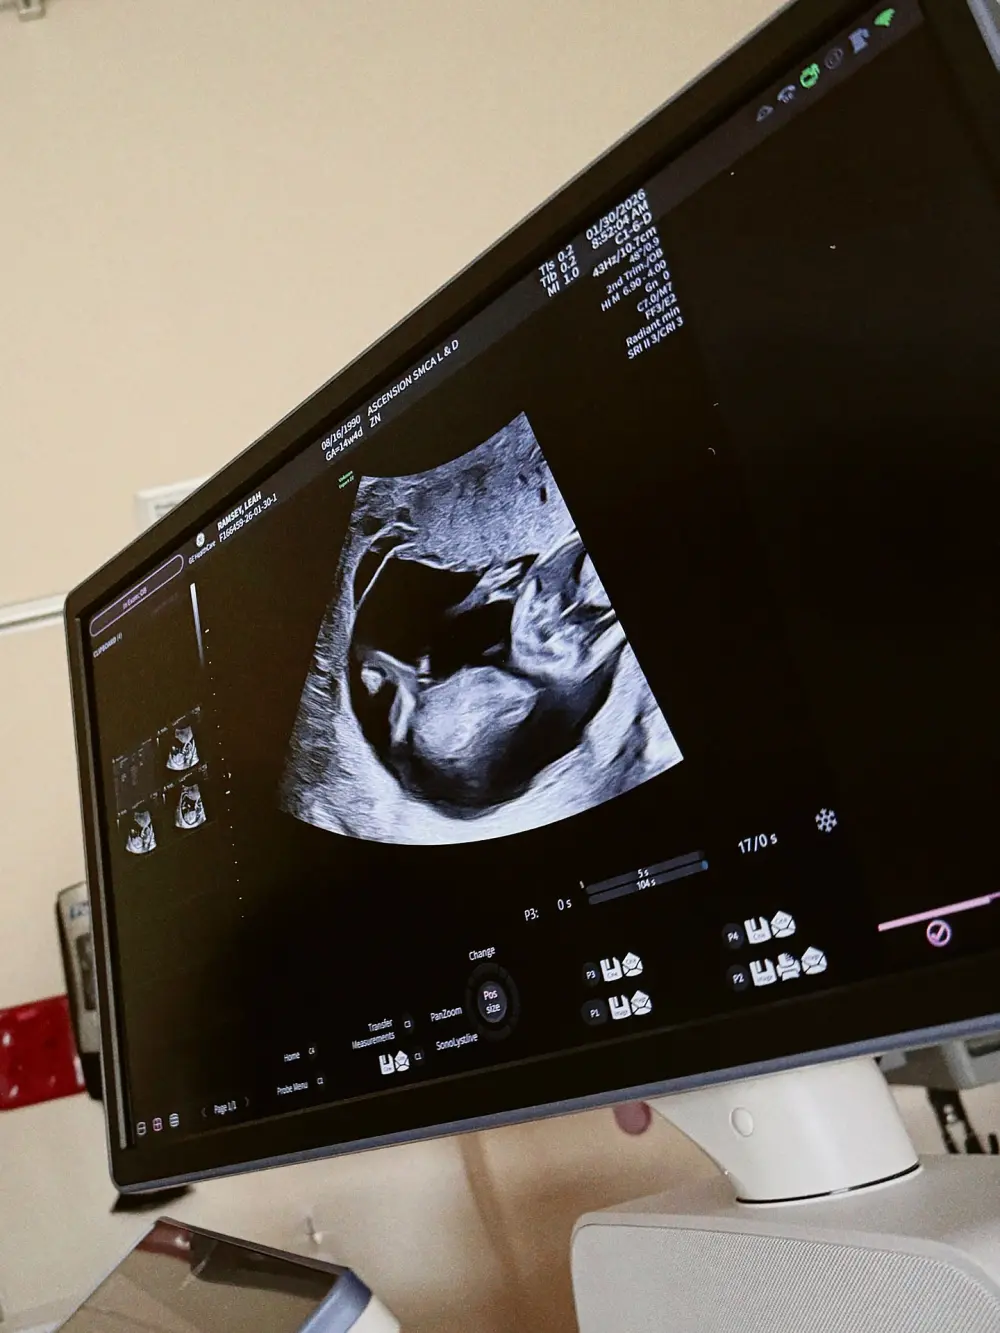

Jay said she was feeling uplifted after seeing their baby girl on the ultrasound, describing it as the “highlight of my week.”

“The little heartbeat and tiny movements gave me the strength I needed,” she continued, before giving a special shout-out to her “incredible” mother-in-law and sister-in-law “who dropped everything” to be there in her time of need.

Fans were overjoyed when he shared on February 3 that their baby was “doing well” after the operation, alongside a pair of ultrasound photos.